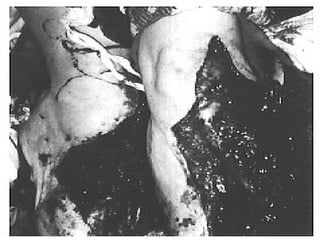

FRACTURA EXPUESTA Es la perdida de continuidad ósea, en  la que el foco de fractura se pone en contacto con el medio ambiente

PARAMETROS DE CLASIFICACION Medio ambiente en que sucedió Tiempo transcurrido entre la lesión y el tratamiento hospitalario El grado de lesión de las partes blandas del miembro afectado o áreas circunvecinas

CLASIFICACION DE LAS FRACTURAS EXPUESTAS Contaminadas : < de 6 hrs de evolución, contaminación por gérmenes del medio ambiente o el agente agresor Infectadas : > de 6 hrs de evolución, reproducción de los gérmenes localmente Complicadas : es la que se acompaña de lesiones en órganos, sistemas, o elementos anatómicos vecinos

CLASIFICACION DE GUSTILLO III:  Lesión extensa de tejidos blandos que afectan al músculo, piel y estructuras neurovasculares, suele existir un alto grado de contaminación, son por alta energía A)  cobertura adecuada de tejido blando del hueso, sin importar el tamaño de la herida

CLASIFICACION DE GUSTILLO B)  Afectación extensa o perdida del tejido blando con exposición del hueso, contaminación masiva y una grave fractura conminuta C)  Se asocia a lesión arterial  que necesita reparación independientemente del grado de lesión del tejido blando

FRACTURA EXPUESTA Esla perdida de continuidad ósea, en la que el foco de fractura se pone en contacto con el medio ambiente

PARAMETROS DE CLASIFICACIONMedio ambiente en que sucedió Tiempo transcurrido entre la lesión y el tratamiento hospitalario El grado de lesión de las partes blandas del miembro afectado o áreas circunvecinas

CLASIFICACION DE LASFRACTURAS EXPUESTAS Contaminadas : < de 6 hrs de evolución, contaminación por gérmenes del medio ambiente o el agente agresor Infectadas : > de 6 hrs de evolución, reproducción de los gérmenes localmente Complicadas : es la que se acompaña de lesiones en órganos, sistemas, o elementos anatómicos vecinos

CLASIFICACION DE GUSTILLOIII: Lesión extensa de tejidos blandos que afectan al músculo, piel y estructuras neurovasculares, suele existir un alto grado de contaminación, son por alta energía A) cobertura adecuada de tejido blando del hueso, sin importar el tamaño de la herida

CLASIFICACION DE GUSTILLOB) Afectación extensa o perdida del tejido blando con exposición del hueso, contaminación masiva y una grave fractura conminuta C) Se asocia a lesión arterial que necesita reparación independientemente del grado de lesión del tejido blando